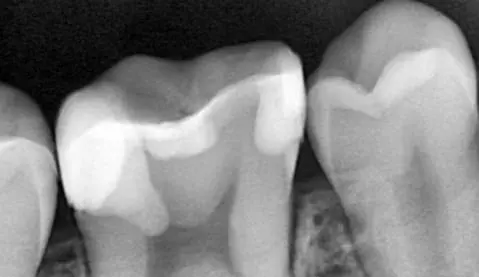

Діагностика і лікувальна тактика: коли можна не втручатись в пульпу, коли можна видаляти її частково і що робити, коли пільпа загинула. Часткова і повна пульпотомія: коли і як це робити? Що робити коли пульпа загинула повністю? Апексифікація і апексогенез, гідроксид кальцію і пробка з МТА. Останні регенераторні тенденції в ендодонтії. Реваскуляризація - що це і коли варто робити?